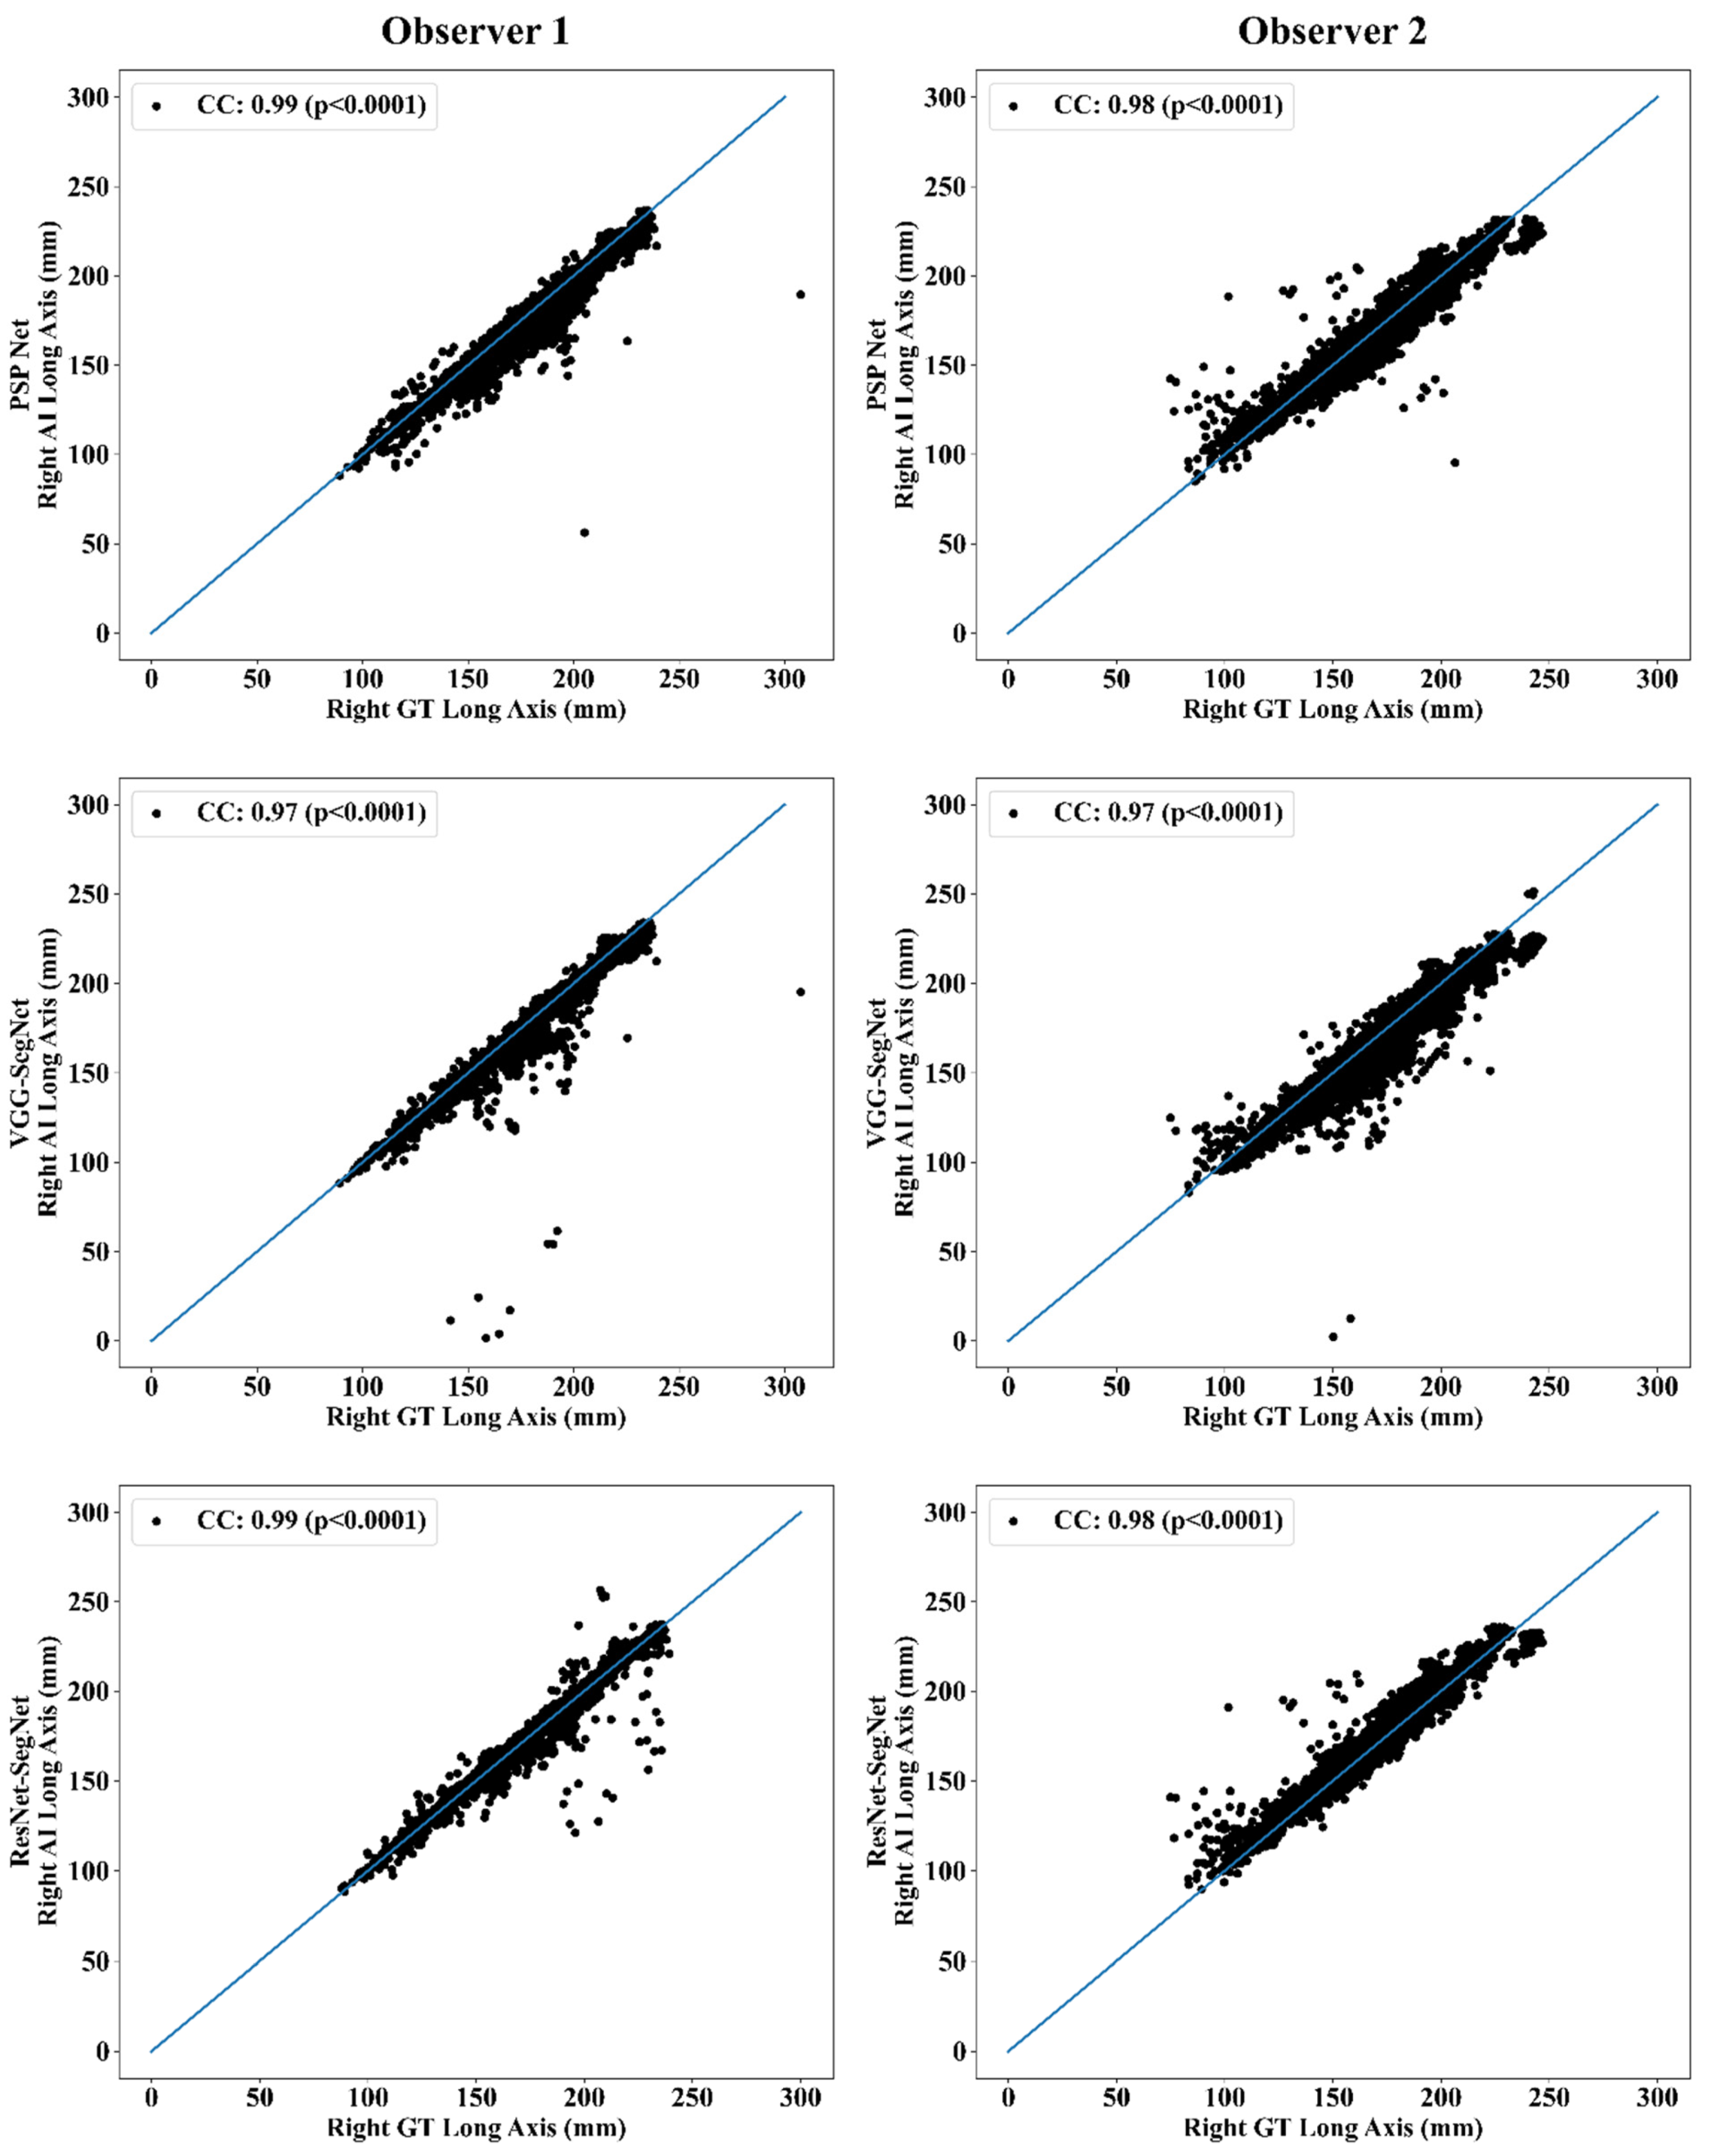

Correlation Plot for Lung Long Axis Error

Statistical Tests